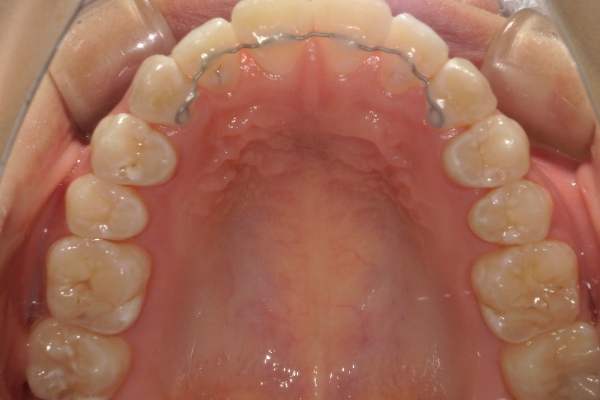

リンガルアーチ

細い弾線で歯を裏側から押すことで、1本〜数本の歯を傾斜移動させる装置です。 軽度の反対咬合や萌出位置の改善に用いられます。

ご自身では取り外しができず、通院時に調節を行うことで少しずつ歯を動かします。

リンガルアーチ単体で使用することもありますし、ワイヤー矯正やフェイシャルマスク等と併用することも多いです。

骨格的に下あごが前下方に長いことが原因で、受け口、開咬(前歯が当たらない)の症状がでていました。また下あごが右にずれており、その影響で上下の歯列正中(真ん中)の大きなずれも生じていました。顎変形症手術も選択肢の一つでしたが、患者さまの希望もあり、下顎左側小臼歯の抜歯をして通常の歯列矯正で治療をしました。

前歯、奥歯の噛み合わせが大きく改善され、上下の歯真ん中が一致しました。食べ物が噛みやすくなったこともですが、歯列の見た目が整った点にも患者さまは満足されていました。